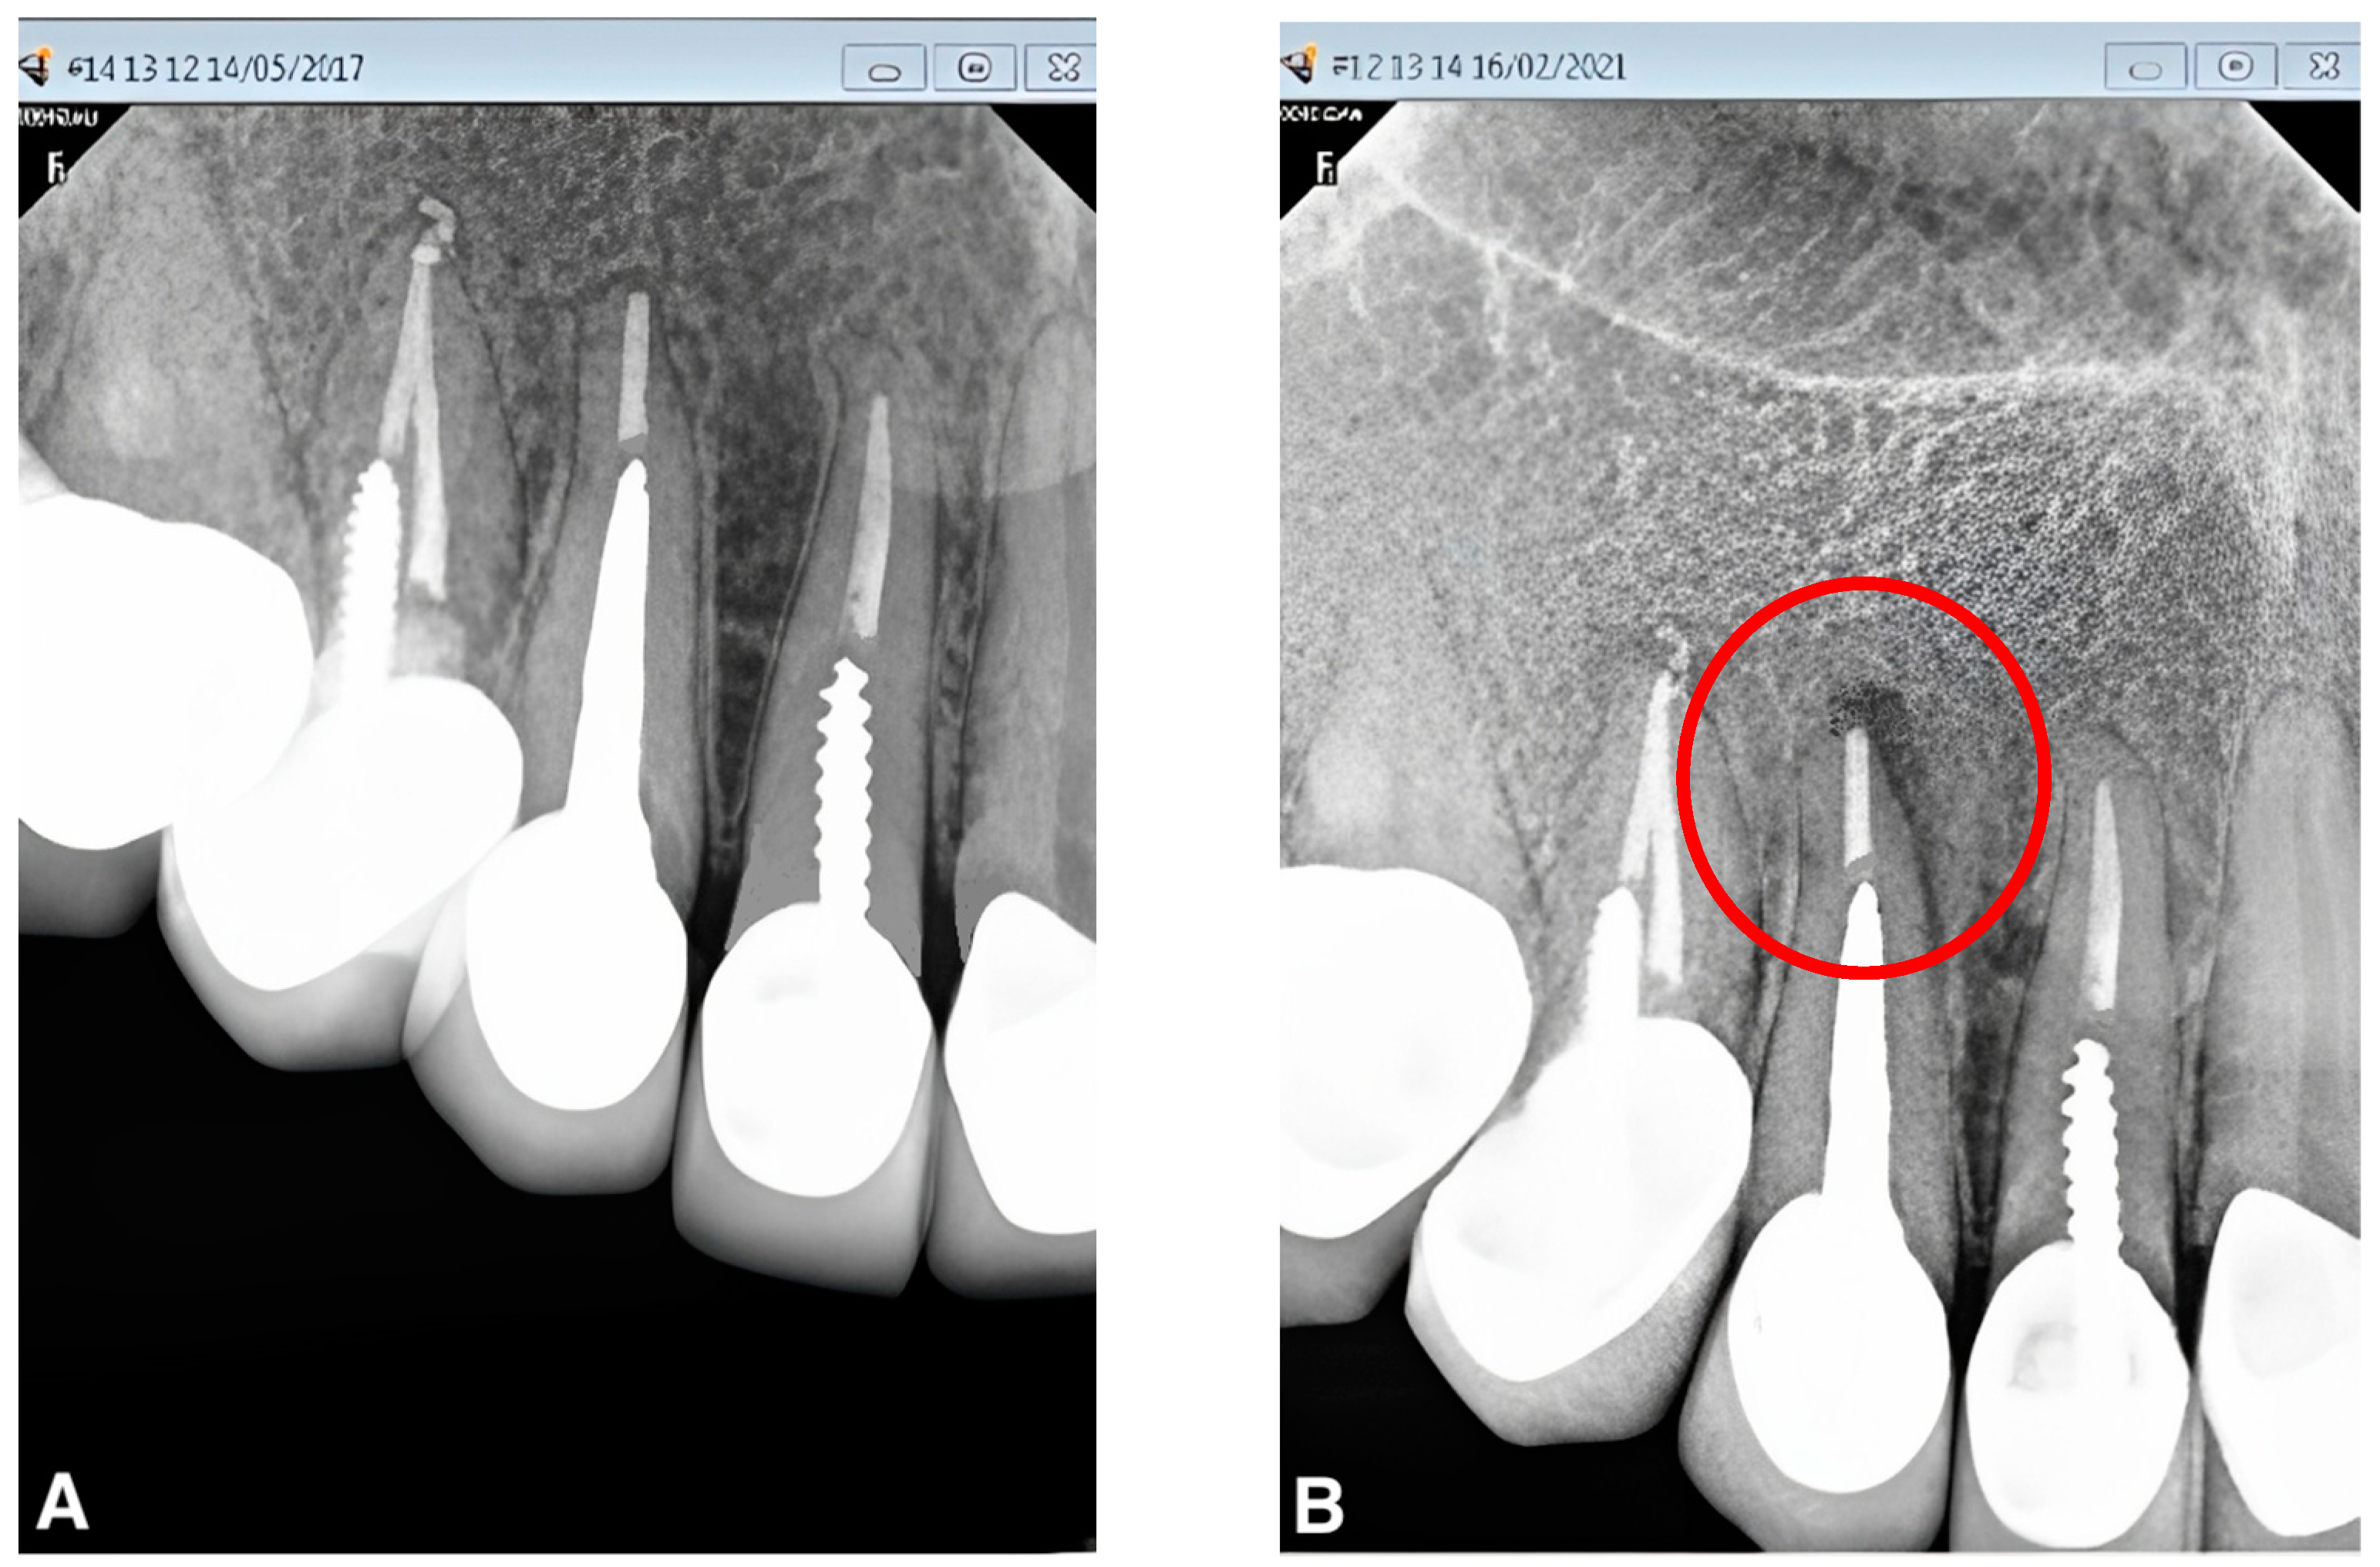

A healthy periapex PAI 1 was described as a healthy periapex, which had the normal width of permanent ligament space and surrounding bone that looked normal. The evaluation of all other PAI scores (2,3,4,5) was mentioned as apical periodontitis. The chi-square test was employed for statistical analysis, with a significance level of p < 0.05. Out of 70 recalled patients, the male students had performed a total of 20 post and core treatments, whereas the female undergraduate students had completed post and core treatments for 50 cases. A total of 90% (n = 18) of the teeth in group I with no gap between the residual gutta-percha and the post were found to be healthy, while 10% (n = 2) were found to be diseased (Figure 1). In group II, there were 66.7% (n = 22) of normal teeth and 33.3% (n = 11) of diseased teeth, with a gap of more than 0 mm to less than 1 mm between the post end and the remaining gutta-percha (Figure 2). However, 58.8% (n = 10) of group III patients with a gap of more than 1 mm between the post end and the remaining gutta-percha were found to be healthy, whereas 41.2% (n = 7) were found to be diseased. (Figure 3). A total of 32% (n = 16) endodontically treated teeth were found diseased and treated by the female students while 68% (n = 34) of teeth were found normal. A total of 20% (n = 4) endodontically treated teeth were found diseased and treated by the male students while 80% (n = 16) of teeth were found normal. (Figure 4 and Figure 5) The quadrant wise treated teeth included for follow up examinations were 36 maxillary anteriors, 8 maxillary posteriors, 12 mandibular anteriors, and 14 mandibular posteriors. Among the maxillary anteriors, 69.4% (n = 25) of teeth were found normal however 30.6% (n = 11) of teeth were found diseased. Among the maxillary posteriors, 50% (n = 4) of teeth were found normal however 50% (n = 4) of teeth were found diseased. Among the mandibular anteriors, 83.3% (n = 10) of teeth were found normal however 16.7% (n = 2) of teeth were found diseased. Among the mandibular posteriors, 78.6% (n = 11) of teeth were found normal however 21.4% (n = 3) of teeth were found diseased. (Figure 4 and Figure 5).

Figure 2. (A,B). Peri-apical radiograph in Group II (gap of >0 but <1 mm between cemented post and remaining gutta-percha) showing the PAI status, before and after 4 years of follow up using the CS-R4 program.